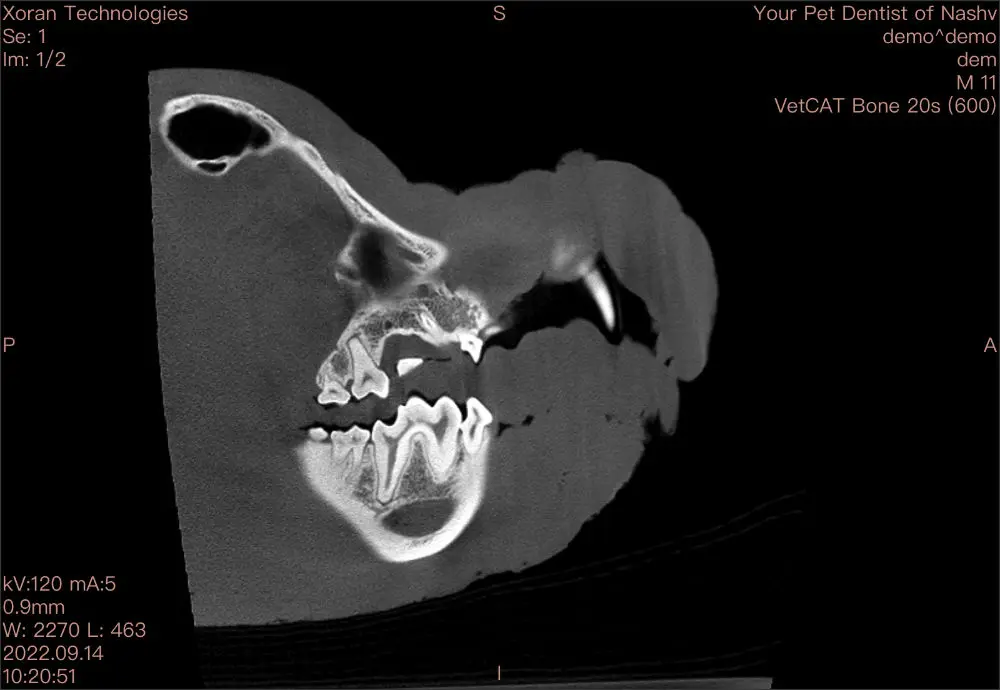

At Your Pet Dentist, we have CBCT (cone beam CT), which is used on all of our patients. The CBCT is used to identify definitive margins for oral cancer surgery as well as to aid in the diagnostics of TMJ pathology.  CBCT is also extremely useful in identifying early endodontic lesions that otherwise could not be seen by conventional dental radiography.